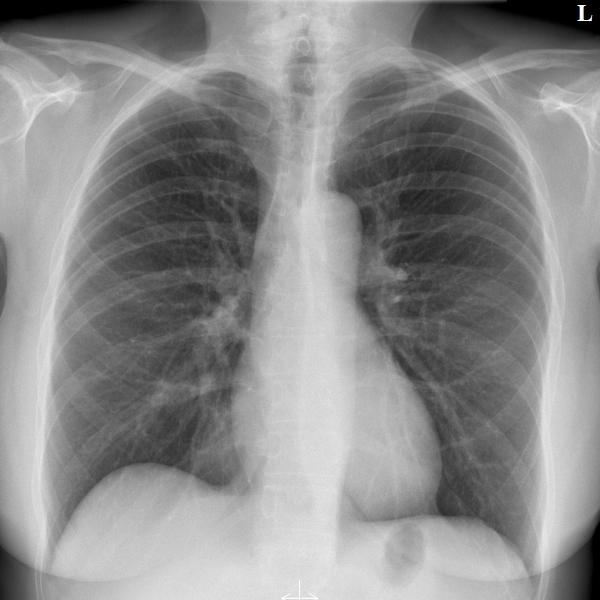

Learn the bony anatomy then test yourself

Learning mode: Hover over the name tags to highlight the relevant anatomy. Once you're ready, head to study mode.